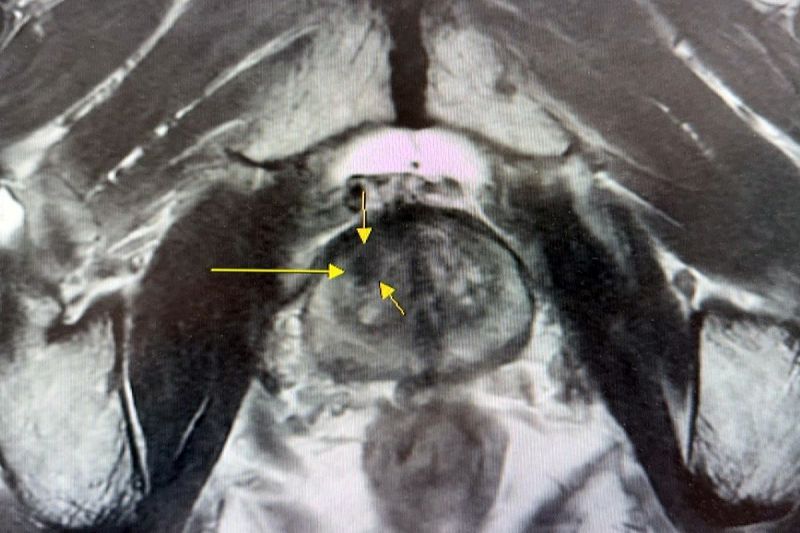

在早期診斷方面,台北慈濟醫院以「核磁造影與超音波影像融合攝護腺切片」,取代傳統「經直腸超音波攝護腺切片」,利用3D影像融合技術將核磁造影顯示的病灶與超音波重疊,讓切片檢查不再是隨機,避免誤判良性或需要重複切片的情形發生。這樣的改變,讓切片準確率提升六至七成,病人得以在早期病灶尚未擴散、轉移時就接受手術治療,平均五年存活率高達九成;而在治療挑戰最高的末期患者中,台北慈濟醫院第四期的五年存活率仍達近六成,整體成效遠高於全國醫學中心。蔡曜州主任說明:「晚期攝護腺癌治療並非單一科別或單一療法可完成,團隊在治療策略上會依據病人確診期別、腫瘤侵犯範圍與身體狀況,整合泌尿科、放射腫瘤科等領域的專業人員,進行個人化治療。其中包括化學治療、放射線治療、賀爾蒙治療以及標靶藥物治療,延長存活期的同時,兼顧病人的生活品質。」